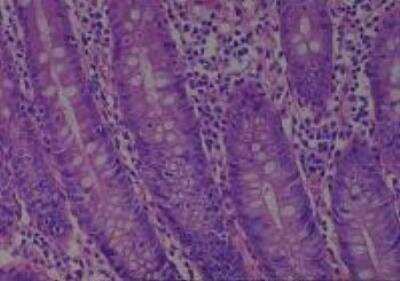

Scientific Data Images for Human Multi Tissue MicroArray (Normal Adjacent)